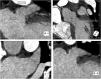

Procedural complicationsThe major complication rate was 8.8% (n=4), consisting in perforation with pericardial effusion requiring pericardiocentesis in 4.4% (n=2) and device embolization (see example in Figure 4) in 4.4% (n=2, one of them leading to cardiac arrest and death), and no major vascular complications occurred. No other procedure-related deaths occurred. The 30-day mortality rate was 2.2% (n=1). Mean length of hospital stay after the procedure was 5.5 days.